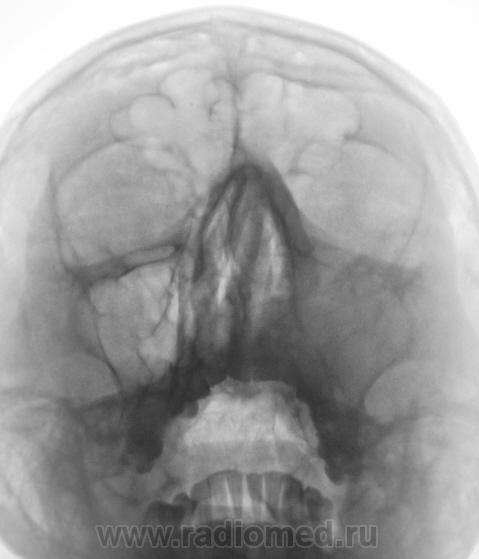

По поводу третьего пациента, остеома или эктопированный зуб?

Mine wrote:

Остеома оказалась.